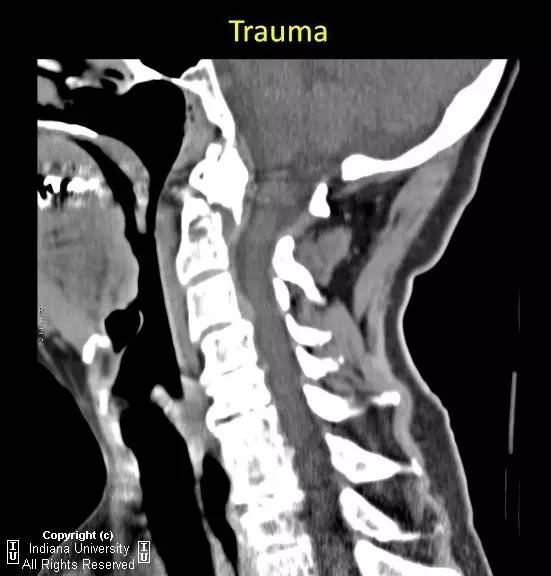

【病例】II型齿状突骨折1例

【影像学表现】

急性横行齿突骨折,C2椎体与齿突尖分离约7mm。齿突尖仍与C1前弓正常排列。

【诊断】II型齿突骨折

Type 2 odontoidprocess fracture